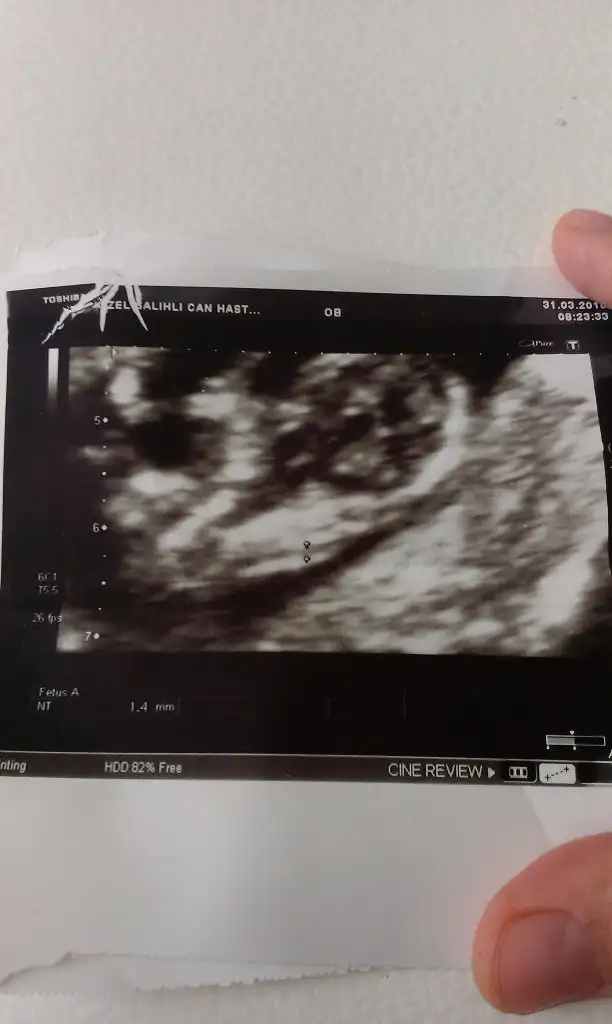

Günaydın kızlar bu da benim miniğim, :) cinsiyet yorumları bekliyorum :) geçen hafta 31 mart salı günü ikili test randevumda 13. haftanın içindeydik, anca bugün yükleyebildim fotosunu. benim hafta döngüm cumadan cumaya :)

Eklentiler

• IMAG0246.jpg

IMAG0246.jpg

2,3 MB · Görüntüleme: 70

çok teşekkür ederim canım, inşallah sağ selamet alırız bebeklerimizi kucaklarımıza. hayırlısı olsun inşallah :) , ultrason görüntüsünü baya evirdi çevirdi gösterdi, ama tam net değil tabiki, ultroson fotoğrafı siyah beyaz tonlamalarında demi, bacak arasını gösterdiğinde yan yana iki tane beyaz nokta vardı, erkek mi kız mı artık kesin olarak nisanın son haftası belli olacak :)